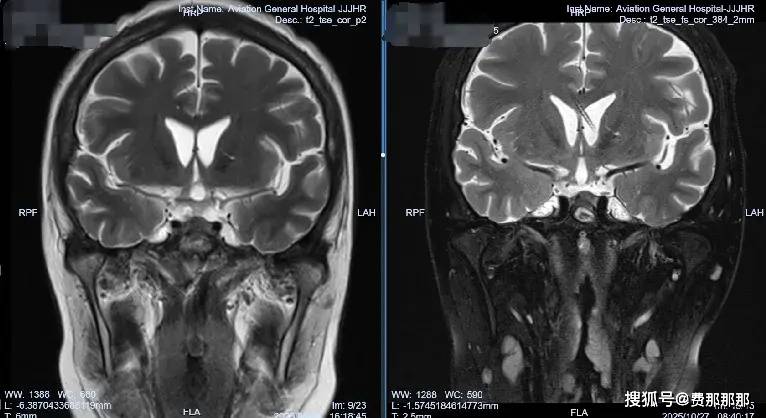

她刚战胜垂体瘤,却陷入更危险的战斗——致命真菌在颅内疯狂生长,三次手术未能遏制,意识一点点消逝。在航空总医院,肖庆主任凭借精准的脑脊液管理策略,为患者打开了生命通道。 35岁的李女士永远不会忘记那个夏